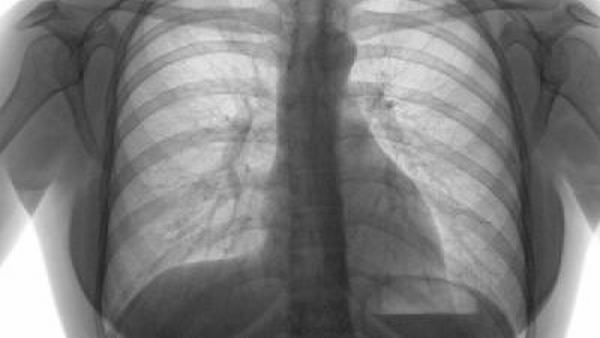

最重要的是,头痛的背后可能隐藏着一些潜在的健康问题。头痛可能是其他疾病或健康问题的症状,例如高血压、中风、脑瘤等。如果头痛问题持续存在或频繁发作,那么就应该及时就医并进行相关的检查,以便排除严重疾病的存在。